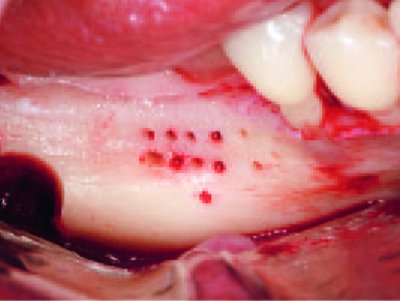

Master-Pin-Control 34pinů+sada k zavádění BMP00, by Prof. Dr. Istvan Urban

Světově nejuznávanější systém pinů pro fixaci membrán.